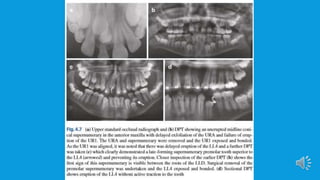

 Routine radiographs such as dental panoramic radiographic, upper standard

occlusal and long-cone periapical can be used in combination to localize a

supernumerary tooth using the parallax technique (horizontal or vertical tube

shift) and may give sufficient information to allow safe removal.

However, if the proximity to developing roots is a concern, assessment of

resorption is required or a decision to whether orthodontic tooth movement

can go ahead without removal of supernumerary tooth, then CBCT may be

indicated.This additional imaging technique has shown to enhance the ability

to localize a supernumerary.